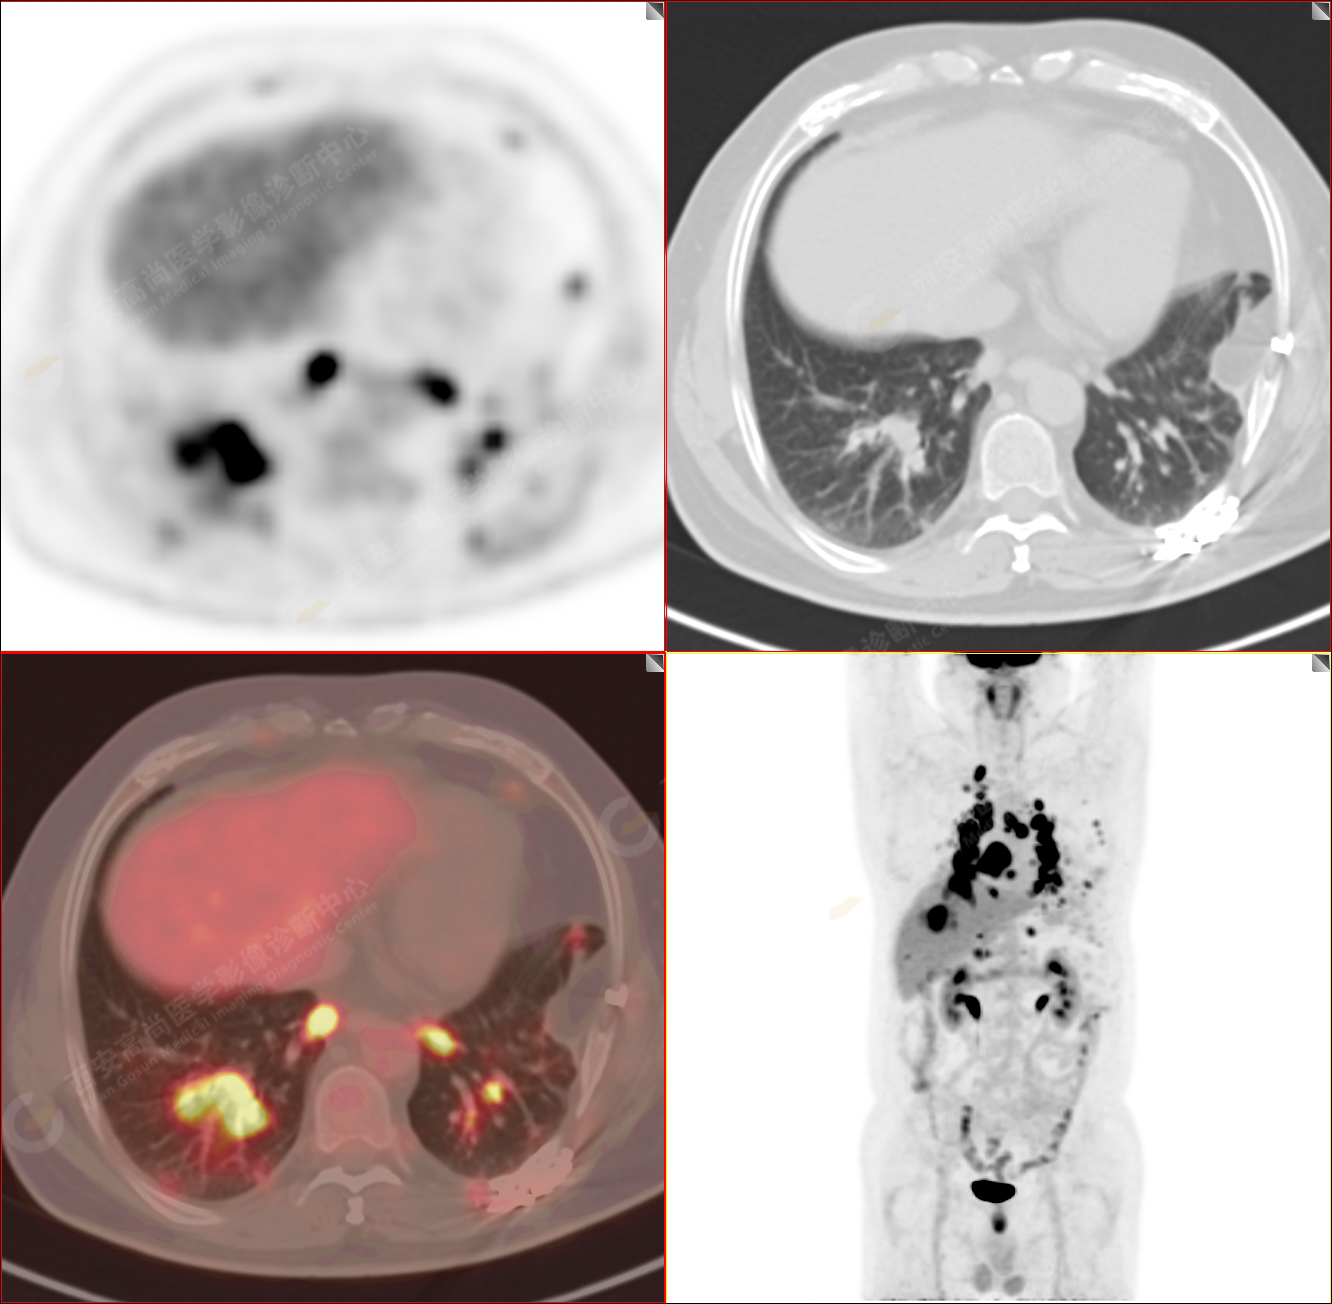

男性,53歲,頭暈半月入院,CT發(fā)現(xiàn)肺內(nèi)腫塊,雙肺多發(fā)大小不等實(shí)性及粟粒樣結(jié)節(jié),雙肺門(mén)及縱隔多發(fā)腫大淋巴結(jié)。病程中無(wú)發(fā)熱、胸悶氣及胸部不適。既往:左側(cè)肋骨外傷史。

PET/CT圖像